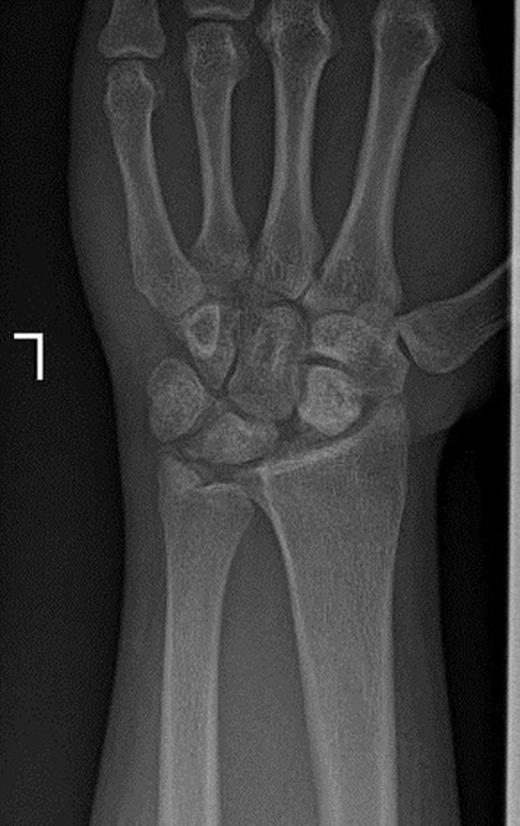

A 19-year old right hand dominant worker man presented after falling from height of about 6 meters onto his left hyperextened wrist. He was a multiple-injured case with closed fractures of femoral shaft and proximal phalanx of left second finger. In exam, wrist swelling was generally moderate with subtle deformity and ecchymosis in volar part. Range of wrist motion was very tender. A thorough serial neurovascular examination showed progressive paresthesia in median nerve territory checked by two points discrimination. Taken X-ray disclosed trans-scaphoid dorsal perilunate fracture dislocation and avulsion fracture of ulnar styloid. Excessive displacement of the lunate to middle third of the forearm and proximal scaphoid with multiple bony fragments to distal third was obvious (Figure 1a & 1b).

Posteroanterior and lateral X-rays of left wrist show perilunate fracture dislocation with excessive proximal displacement of lunate and proximal scaphoid. Loss of carpal height with broken Gilula’s arcs is obvious.